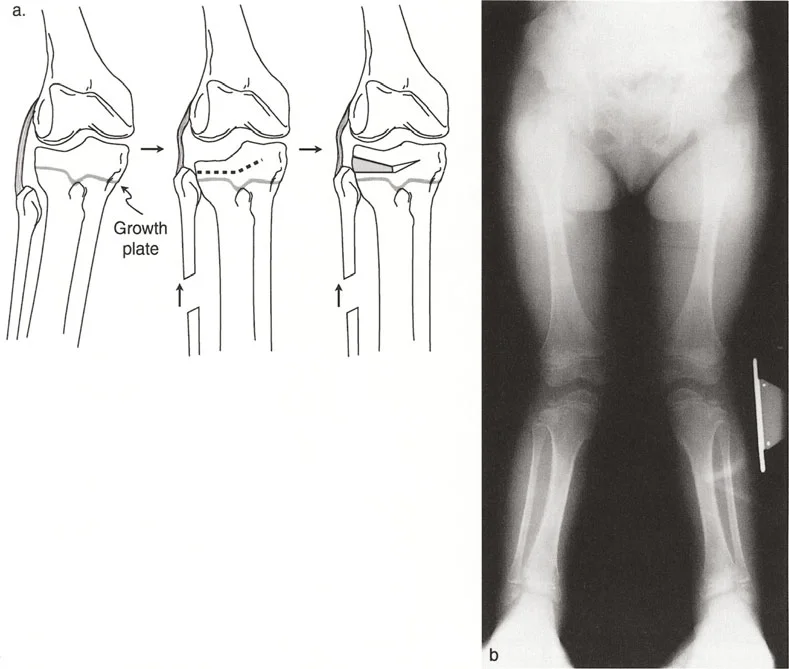

إذا كان التصحيح داخل المفصل (مثل رفع الهضبة المباشر) قيد النظر لاستعادة تطابق المفصل، فيجب وصف السطح المفصلي بخطين منفصلين - واحد لكل هضبة. يسمح هذا للجراح بحساب بالضبط عدد الملليمترات من الارتفاع ودرجات الميل الزاوي المطلوبة للجزء المنخفض.

إعادة المحاذاة داخل المفصل رفع الهضبة

إذا قرر الجراح أن هندسة مفصل الركبة غير مقبولة - بسبب عدم استقرار سريري شديد، أو خلع متكرر، أو درجة كبيرة ستدمر الغضروف الهلالي والغضروف المفصلي حتماً - فيجب تحويل التخطيط والتنفيذ إلى تصحيح حقيقي داخل المفصل.

تسلسل التخطيط لرفع الهضبة

تتطلب جراحات قطع العظم داخل المفصل مهارة فنية عالية وتخطيطاً قبل الجراحة لا تشوبه شائبة.

- تحديد مستوى الهدف: ارسم خطاً يمتد من اللقمة أو الهضبة الطبيعية غير المنخفضة مباشرة نحو الجانب المنخفض. يصبح هذا الإ